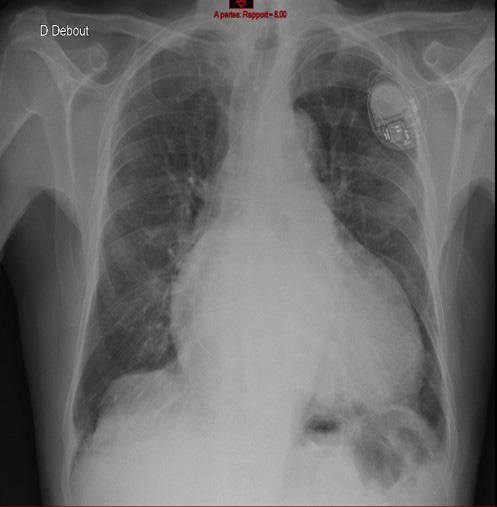

Décision d’implantation de stimulateur cardiaque simple chambre au niveau du SIV (échec de stimulation branche gauche au vu de la dilatation majeure de l’oreillette droite) (Figure 8).

Fréquence de stimulation réglée à 80 bpm afin d’améliorer l’hémodynamique (au vu d’une dyspnée importante à l’effort).

Les troubles conductifs et troubles du rythme sont fréquents dans l’amylose cardiaque.

Figure 8 : Implantation de stimulateur cardiaque